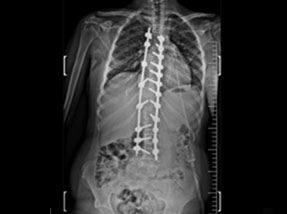

• Pre-SurgeryBefore

• Post SurgeryAfter

Case 1